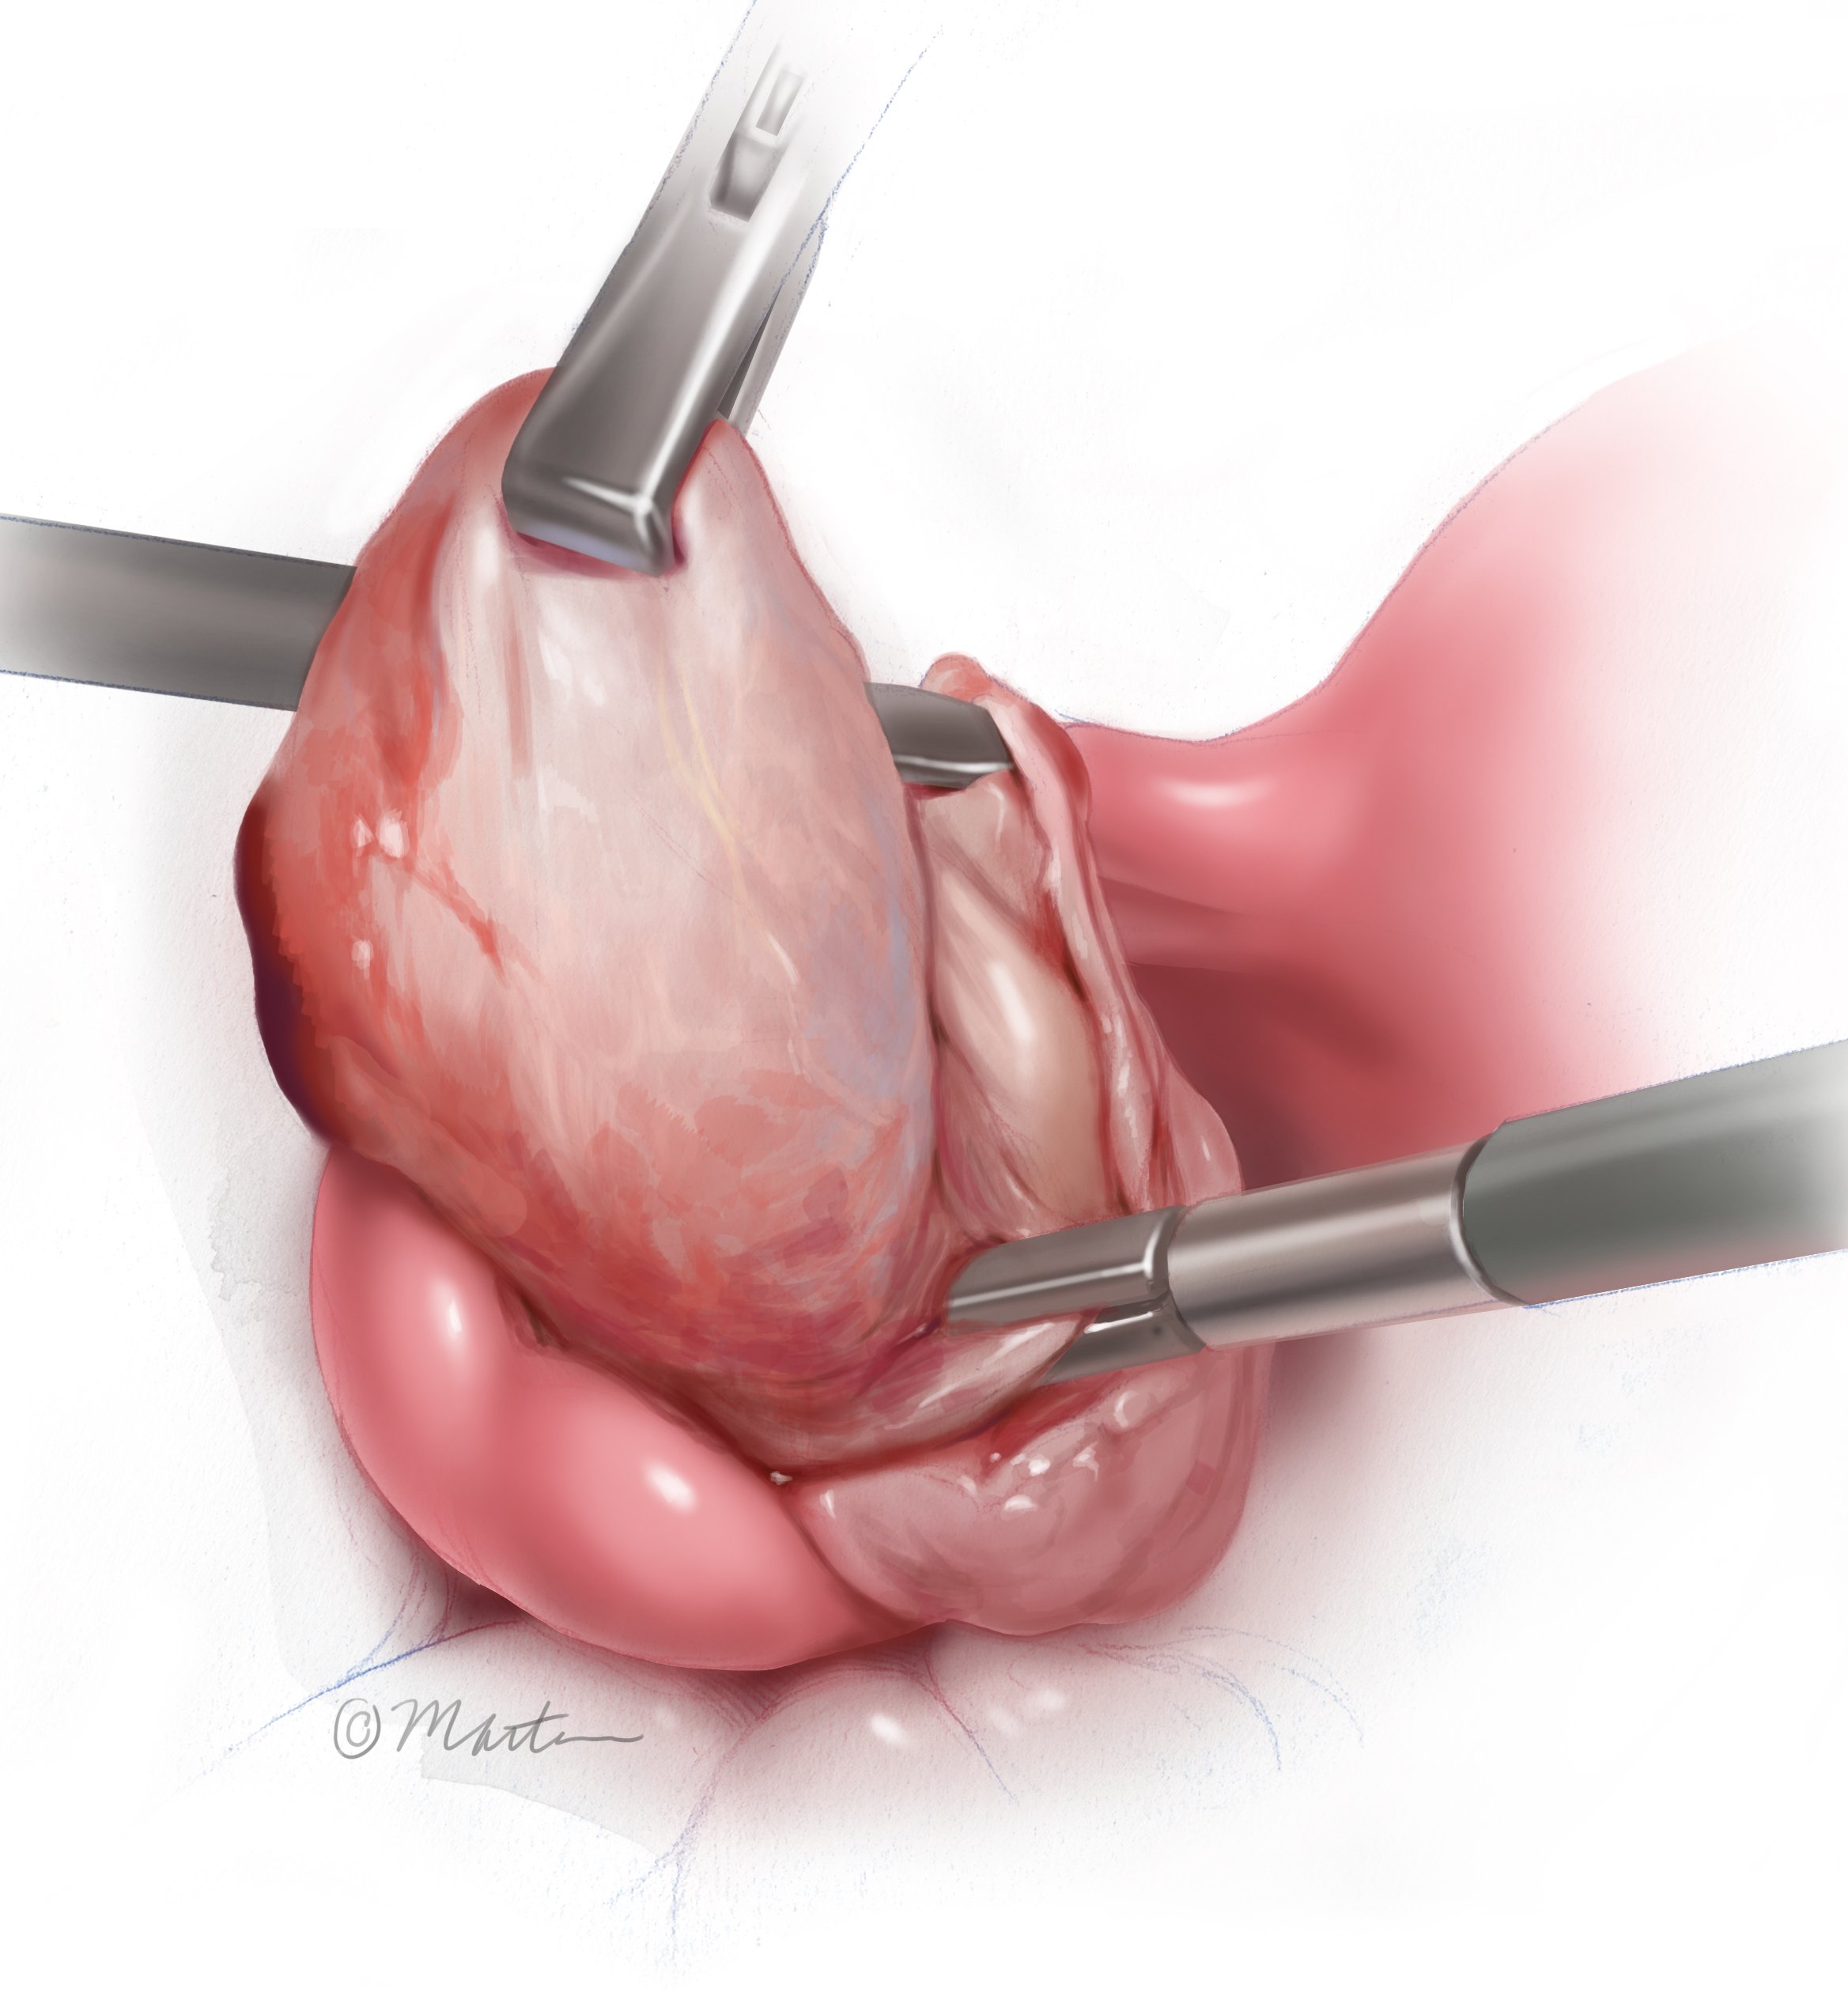

Ectopic Pregnancy

Ovarian Cystectomy